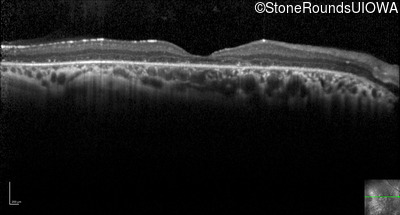

Optical Coherence Tomography - Right - 20/63 +1

Exemplar / OCT Stack